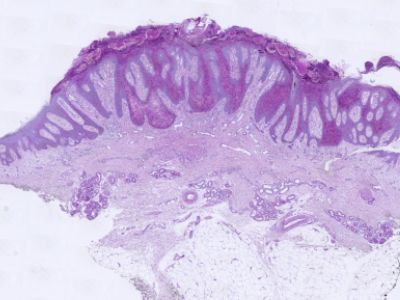

Histologie:Epidermale hyperplasie, verlengde retelijsten,

spongiose, PAS-kleuring: clear cells met glycogeenstapeling. Zie ook de

ingescande PA-coupe van de

afdeling pathologie van de University of

Toronto.

![Histologie clear cell acanthoma (click on photo to enlarge) [source: Kevin Kwee / Afdeling Pathologie MUMC] Histologie clear cell acanthoma](../../../pacoupes/thumbnails/clear-cell-acanthoma.jpg) |

![Histologie clear cell acanthoma (PAS kleuring) (click on photo to enlarge) [source: Kevin Kwee / Afdeling Pathologie MUMC] Histologie clear cell acanthoma (PAS kleuring)](../../../pacoupes/thumbnails/clear-cell-acanthoma-PAS.jpg) |

ingescande coupe (zoom) |

iingescande coupe (zoom) |

Bron

hoge resolutie PA-foto's: Kevin Kwee en Afdeling Pathologie MUMC. Klik

op de afbeelding om in te zoomen.